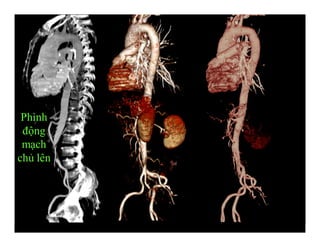

Phình

động

mạch

chủ lên

Phình động mạch chủ bụng-Hình tái tạo 3 D

Phình động mạch chủ

bụng